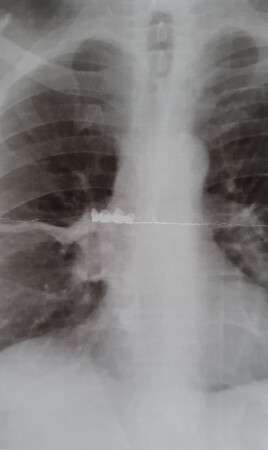

Автор сообщает, что к медикам обратился мужчина и сообщил, что он проглотил зубной протез. Проведенный рентген брюшной полости показал отсутствие инородного тела. В течение всего периода с того момента, как мужчина проглотил протез, у него наблюдался приступообразный кашель. С подозрением на COVID-19 пациенту сделали рентгенограмму грудной клетки и выявили инородное тело, находившееся в правом бронхе. Под местной анестезией мужчине сделали операцию и извлекли зубной протез.